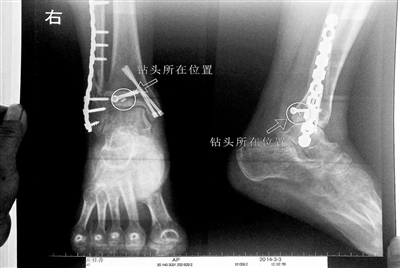

胡女士的腿部X光圖

看著X光片中自己腿內(nèi)的異物,胡女士就感到莫名的擔憂。胡女士于2013年3月在北京市豐臺區(qū)右安門醫(yī)院進行了一次骨折手術(shù),術(shù)后醫(yī)生才發(fā)現(xiàn)手術(shù)時用來打眼用的鉆頭不慎遺留在了胡女士的骨頭中,并且無法取出。

近日,在豐臺區(qū)右安門醫(yī)院,北京青年報記者見到了胡女士,她走起路來顯得一瘸一拐,腿腳并不利索。在她帶來的X光片上,可以清晰地看到,有一個異物存在于腿內(nèi)部。

“我當時就嚇蒙了,怎么會有一個鉆頭在骨頭里?”胡女士余悸未消地說,第二天拍攝的X光片顯示,2厘米左右的鉆頭遺留在她右腳腳踝上部的骨頭內(nèi)。

胡女士說,當時旁邊的醫(yī)生勸慰自己,稱鉆頭留在腿里并不會有什么問題。出院后,胡女士每個月都會來醫(yī)院做復查,拍X光片。她說,每次都能夠清晰地看見自己骨頭里的那個明晃晃的“小東西”。